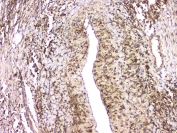

IHC staining of FFPE human stomach tissue with HECTD3 antibody at 1ug/ml. HIER: boil tissue sections in pH6, 10mM citrate buffer, for 10-20 min and allow to cool before testing.